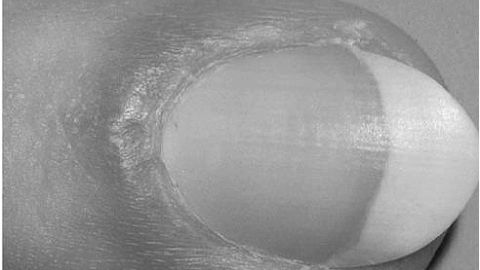

Першим фактором, що насторожує є зміна кольору нігтя. При поверхневому ураженні він ставати білим або жовтуватим. Це відбувається через скупчення рогових мас між ложем і нігтьової пластиною. Ця форма грибка в більшості випадків вражає долоні у жінок. Якщо збудниками хвороби є грибки пліснявий групи, колір нігтя набуває зеленуватий відтінок. При ураженні нігтів дріжджоподібними грибами Candida вони набувають фіолетового, коричневий і навіть чорний колір.